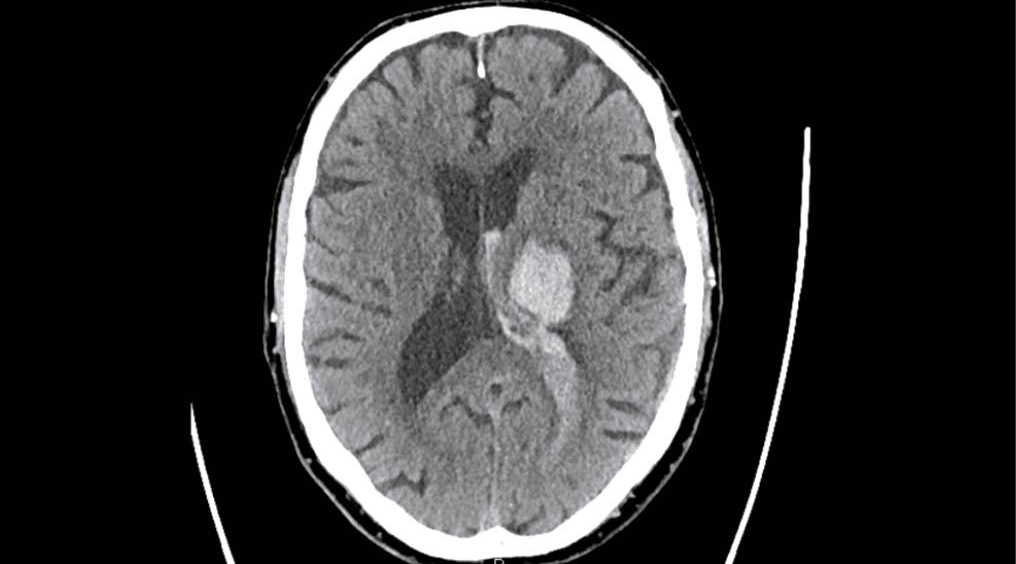

Arterielle Hypertonie verursacht einen Umbau der Gefässwand, fördert Atheromatose und Veränderungen der Endothelfunktion sowie der zerebralen Autoregulation. In der Folge entstehende Gefässrupturen führen zu Hirnblutungen (Abb. 1). Embolien, lokale Thrombusbildung oder seltener eine hämodynamische Insuffizienz verursachen Hirninfarkte (Abb. 2). Durch chronische mikroangiopathische Schäden entstehen Marklagerhyperintensitäten, Mikroinfarkte/-blutungen und neurodegenerative Prozesse wie Hirnatrophie. Es steigt nicht nur das Hirnschlag- aber auch das Demenzrisiko vom vaskulären aber auch vom Alzheimer Typ (8, 9).